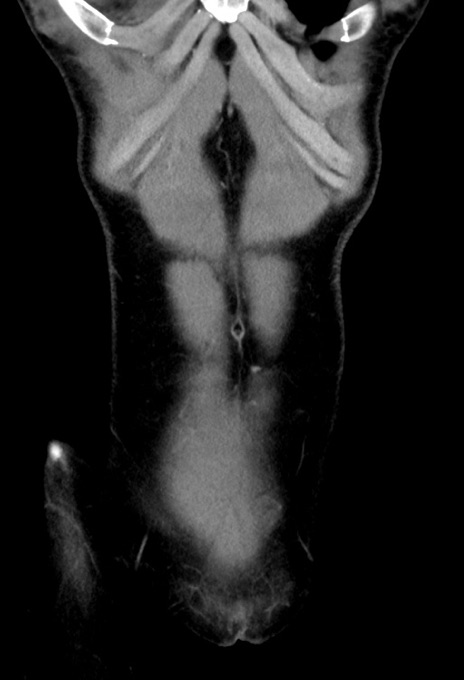

症例17(冠状断像)

症例

【症例】20歳代女性

【主訴】嘔吐、下腹部痛

【現病歴】昨日夕食後に嘔吐し下腹部痛が出現。本日になっても嘔吐持続し改善しないため来院。

【既往歴】なし。

【身体所見】意識清明、BT 37.2℃、BP 108/67mmHg、腹部:平坦、やや硬、下腹部正中から右にかけて圧痛あり、反跳痛軽度あり、tapping pain(+)。

【データ】WBC 13600、CRP 14.94